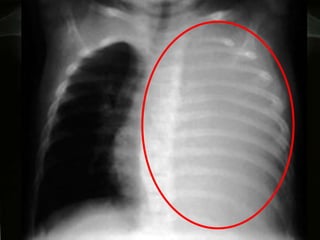

DIAGNÓSTICO POR  IMAGENOLOGÍA Oscar Asensio de la Cruza, Javier Blanco Gonzálezb, Antonio Moreno Galdóc, Javier  Pérez Fríasd, Antonio Salcedo Posadase, Lidia Sanz Borrellf Radiografía   PA y L :  hallazgo típico del derrame pleural:  obliteración del ángulo costofrénico posterior   que da una  imagen de menisco , bien notorio  >  de 175 ml de líquido .

RADIOLOGIA:  Detecta la presencia del derrame y sugiere su etiología  En la radiografía PA y lateral, el hallazgo típico del derrame pleural es la obliteración del ángulo costofrénico posterior (imagen de menisco). Un derrame masivo produce desviación contra lateral del mediastino; la causa más frecuente es la malignidad

RADIOLOGIA:  Se observan hallazgos atípicos: aplanamiento o desplazamiento en la cúpula  aumento de la distancia del diafragma a la burbuja gástrica (2 cm) u opacidad eliptoidea o &quot;pseudotumor&quot;. La proyección en decúbito lateral ayuda en casos de duda.  Importante cuando se va a puncionar (seguridad). .